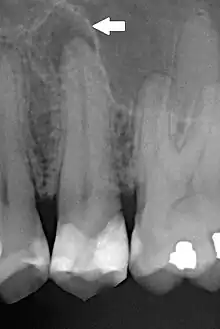

Periapical dental radiograph showing chronic periapical periodontitis on the root of the left maxillary second premolar. Note large restoration present in the tooth, which will have undergone pulpal necrosis at some point before the development of this lesion.

The radiographic features of periapical inflammatory lesions vary depending on the time course of the lesion. Because very early lesions may not show any radiographic changes, diagnosis of these lesions relies solely on the clinical symptoms. More chronic lesions may show lytic (radiolucent) or sclerotic (radiopaque) changes, or both.